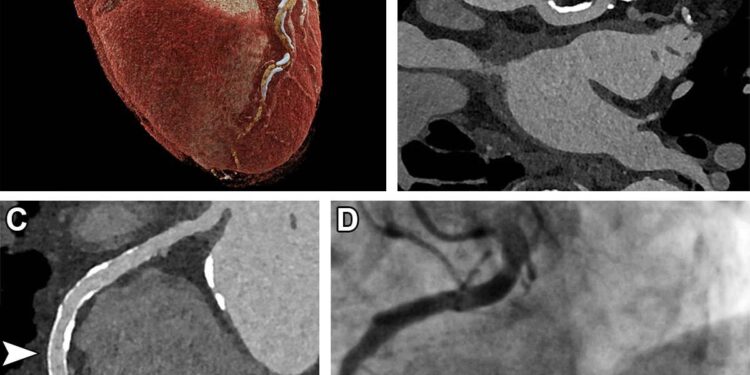

Coronary computed tomography angiography (CCTA) has been shown to significantly enhance patient engagement compared to traditional cardiovascular risk scores. Recent studies indicate that patients receiving personalized imaging results from CCTA are more motivated to adopt lifestyle changes and adhere to recommended medication regimens. Unlike conventional risk calculators, which provide abstract percentage estimates, CCTA offers a tangible visualization of coronary artery health, fostering a stronger emotional and cognitive response that translates into real-world health improvements.

Leading cardiology experts advocate for the integration of Coronary Computed Tomography Angiography (CCTA) alongside traditional cardiovascular risk scoring tools to enhance preventive strategies. Unlike conventional risk scores, which rely heavily on demographic and biochemical factors, CCTA provides a direct visualization of coronary artery plaque burden and morphology. This detailed anatomical insight has been shown to significantly influence both clinician prescribing behavior and patient adherence to lifestyle modifications.